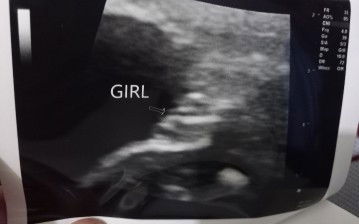

Gender at 23 weeks

Sure na po kaya? Taken at 23weeks during CAS